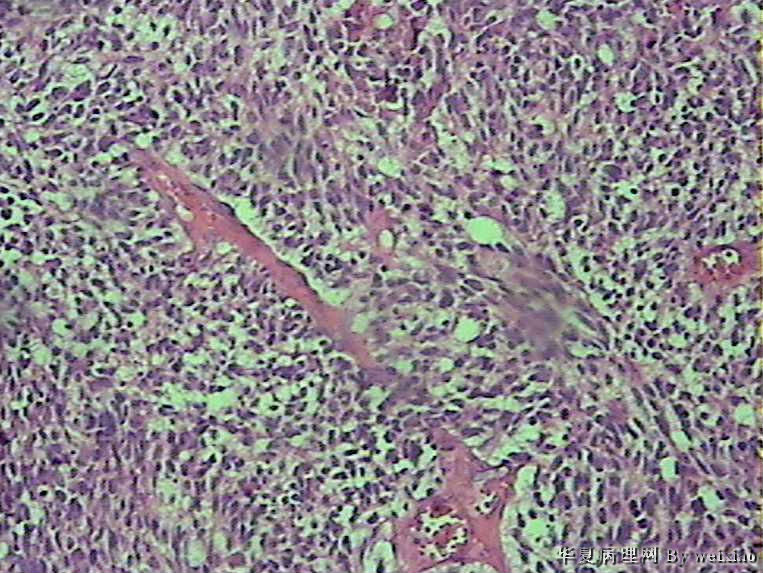

病史:男45岁,头痛2个月,手术所见:额叶占位性病变,与周围正常脑组  织的界限不清。

大体:灰白色碎组织一堆,质软,大小:2.5*1.8*1.3cm

• 额叶肿瘤图3

图3

×参考诊断

胶质母细胞瘤

会诊胶质母细胞瘤

The tumor cells are kind of spindle, need to rule out gliosarcoma, you need to check MRI films, do immunostain for GFAP, and vimentin. The vascular proliferation (VP) supports GBM.

肿瘤细胞呈梭形,血管增生明显,有坏死,符合胶质母。